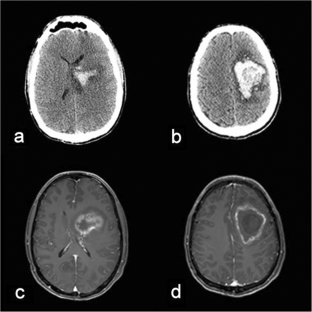

Fig. 1